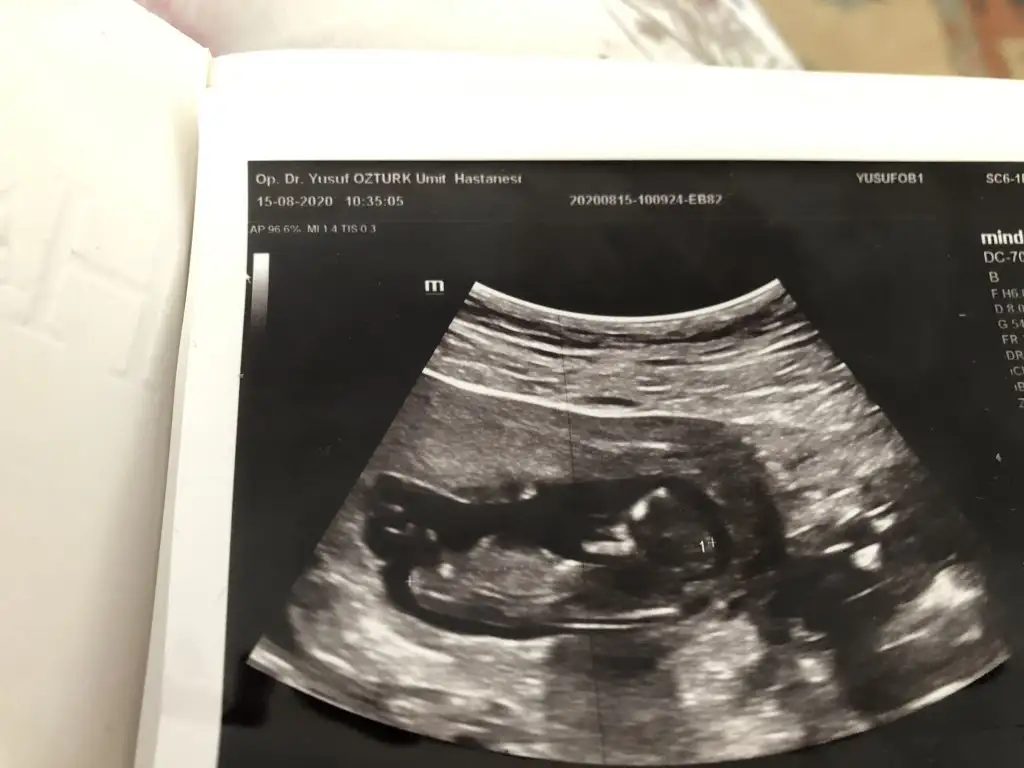

Buna göre kız gibi gibi gibimerhaba şuan 9 hafta 6 günlüğüz belli olmadığını biliyorum hiçde farketmiyor sağlıklı olsun Allahtan tek dilediğim bu.. Ama merak da ediyorum tahmininizi alsam bir sonrski kontrolüm 3 hafta sonra yine atarım görüntüsünü ama şimdi belki birşey diyebilirsiniz

Sanki erkek gibi emin olamadım Dr + getirmiş nubuna çok zor tahmin etmek 12-13 hafta olursa paylasinKızlar benim bebeğimin cinsiyetinide tahmin eder misiniz 11+3te cekildi. Ve aynı gün kalp atisida 168 geldi.Eki Görüntüle 2677122